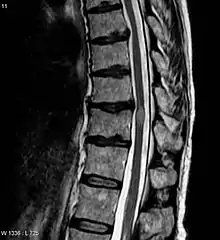

Myelitis has an extensive differential diagnosis. The type of onset (acute versus subacute/chronic) along with associated symptoms such as the presence of pain, constitutional symptoms that encompass fever, malaise, weight loss or a cutaneous rash may help identify the cause of myelitis. In order to establish a diagnosis of myelitis, one has to localize the spinal cord level, and exclude cerebral and neuromuscular diseases. Also a detailed medical history, a careful neurologic examination, and imaging studies using magnetic resonance imaging (MRI) are needed. In respect to the cause of the process, further work-up would help identify the cause and guide treatment. Full spine MRI is warranted, especially with acute onset myelitis, to evaluate for structural lesions that may require surgical intervention, or disseminated disease.[11] Adding gadolinium further increases diagnostic sensitivity. A brain MRI may be needed to identify the extent of central nervous system (CNS) involvement. Lumbar puncture is important for the diagnosis of acute myelitis when a tumoral process, inflammatory or infectious cause are suspected, or the MRI is normal or non-specific. Complementary blood tests are also of value in establishing a firm diagnosis. Rarely, a biopsy of a mass lesion may become necessary when the cause is uncertain. However, in 15–30% of people with subacute or chronic myelitis, a clear cause is never uncovered.[9]